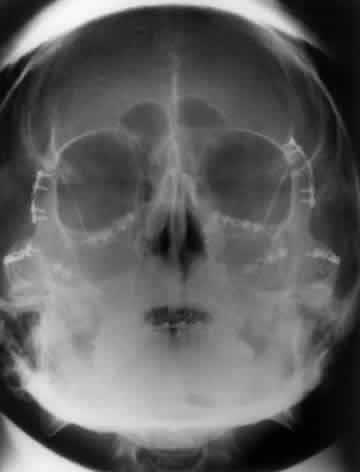

The posterior segment of the lateral wall courses posterior medially and can be seen in anterior projections such as the Caldwell view. This view allows direct visualization of the greater sphenoid wing contribution to the lateral wall. Bone density changes in the greater wing of the sphenoid, such as from a meningioma, can be detected. Fractures of the lateral orbital wall can occur from blunt trauma to the malar prominence. The zygomatic complex fracture (tripod) results from separation of the zygomatic-frontal, zygomatic-temporal, and the zygomatic-maxillary sutures. These fractures are associated with an inferior displacement of the malar prominence and a rounded lateral canthus (Figs. 8 and 9).

Fig. 8. A zygomatic complex fracture (tripod) after blunt trauma to the right cheek. Note the right zygoma is inferiorly displaced. (a, zygomatic-frontal suture separation; b, orbital rim disruption; c, opacification of maxillary sinus)

Fig. 9. Bilateral zygomatic complex and LeFort II fracture after reduction using fixation plates. Caldwell projection shows good alignment of orbital margin and zygomatic bones.